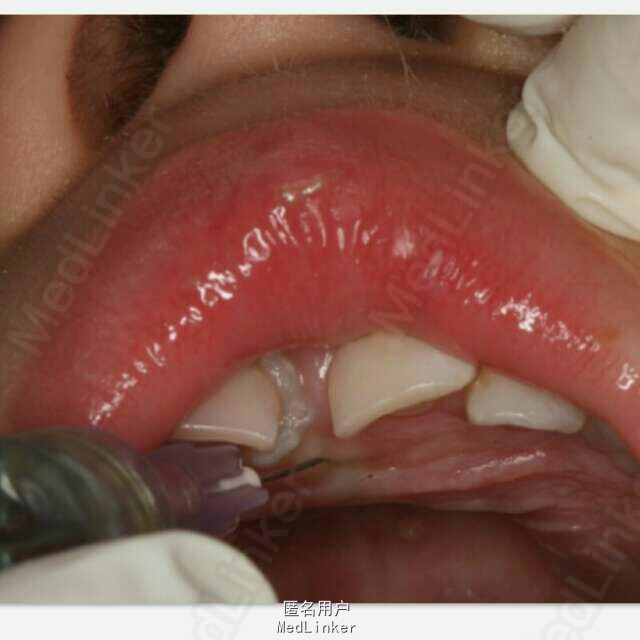

患者、王xx、4岁、男孩。主诉:上前牙松动,要求治疗。现病史:一个月前、患儿不慎碰墙,导致上前牙受伤,当时未做任何处理,最近两天,患儿感觉上前牙松动,轻微疼痛,遂来我院儿牙科就诊。专科检查:右上乳Ⅰ松动一度。右上乳Ⅰ近中侧有一畸形牙尖。x线根尖片:右上乳Ⅰ根尖1/3折断,其近中有一多生牙,该多生牙压迫右上乳Ⅰ近中根面吸收。同时发现左上乳Ⅰ也有一颗多生牙。诊断:(1)右上乳Ⅰ根折。(2)多生牙。处理:1)建议拔除右上乳Ⅰ和其下方多生牙,待患儿到能配合的年纪再拔除左侧乳Ⅰ下方的多生牙。2)同时拔除右上乳Ⅰ和两枚多生牙。给患儿目前讲明两种方案的利弊,患者选择第二套方案。 术前建议患儿母亲做全麻拔除。患者母亲不同意全麻,害怕对孩子大脑有影响。局麻可能因患儿配合欠佳,导致手术终止。患者同意可能出现的意外导致手术终止。签手术知情同意书。